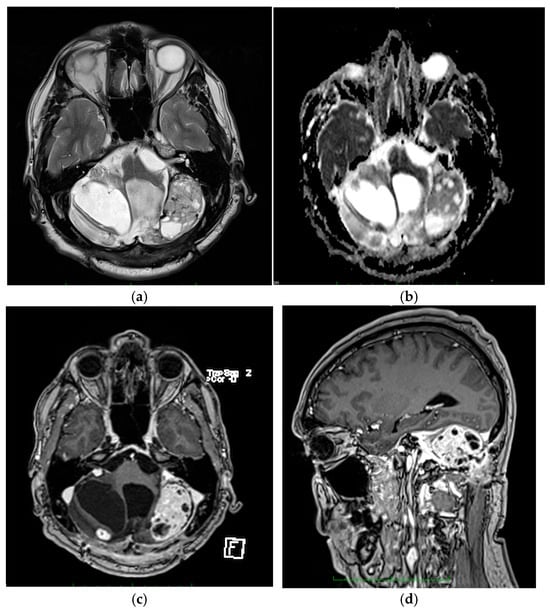

3.1.2. Patient Two